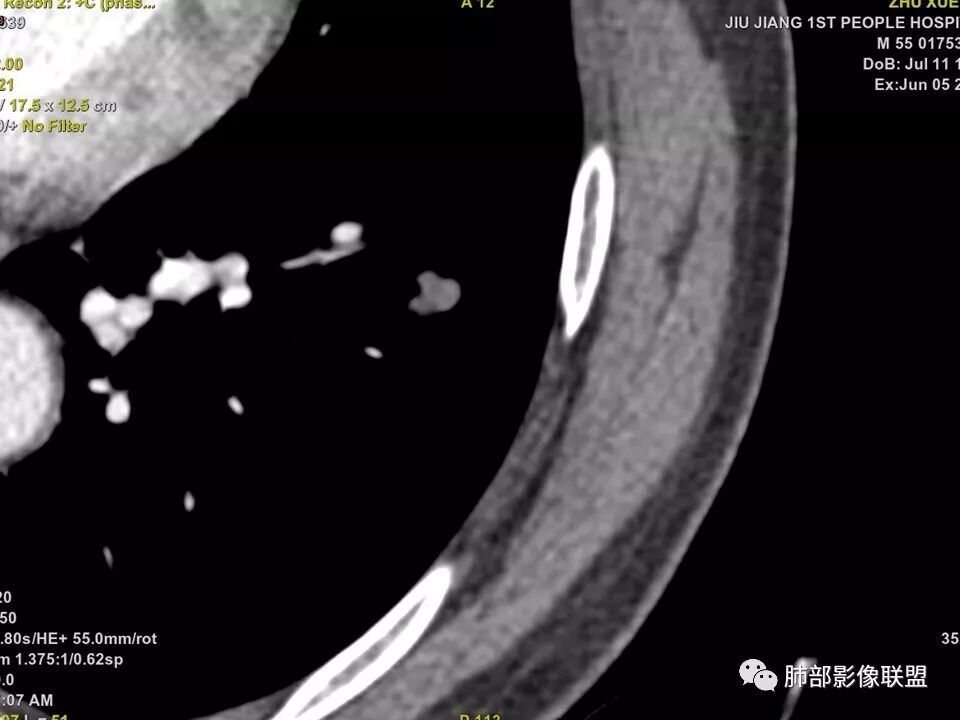

中年男性,左肺下叶不规则实性结节,有分叶及棘状凸起,支气管截断,轻度不均匀强化,考虑鳞癌,鉴别炎性肉芽肿。

左肺下叶前内基底段结节 深分叶和脐凹 表面部分膨隆 部分收缩 支气管截断 轻度强化 中央有坏死 考虑鳞癌 鉴别炎性结节

左肺下叶前内基底段结节,轮廓凹凸不平,局部边缘平直,密度不均,近段支气管阻塞,增强前后CT值无明显变化,考虑肉芽肿,结核?腺癌代排

左肺下叶前基底段结节,病灶边缘分叶,边缘平直,u型征,可见气管截断,增强可见病灶边缘血管,平扫ct值低,轻度强化。考虑良性病变。

实性结节,以收缩为主,强化弱,支气管截断面呈凹面,浅分叶,肉芽肿性炎

典型CT特征包括:(1)圆形或椭圆形边界清楚的病灶。(2)大小1~4cm,有轻微分叶改变。(3)较均匀的软组织影,多伴有钙化。(4)无毛刺,卫星灶及肺门或纵隔淋巴结肿大。(5)CT增强扫描无强化或轻度强化,其强化可能与软骨瘤间质中的薄壁血管或周围慢性炎症反应有关。